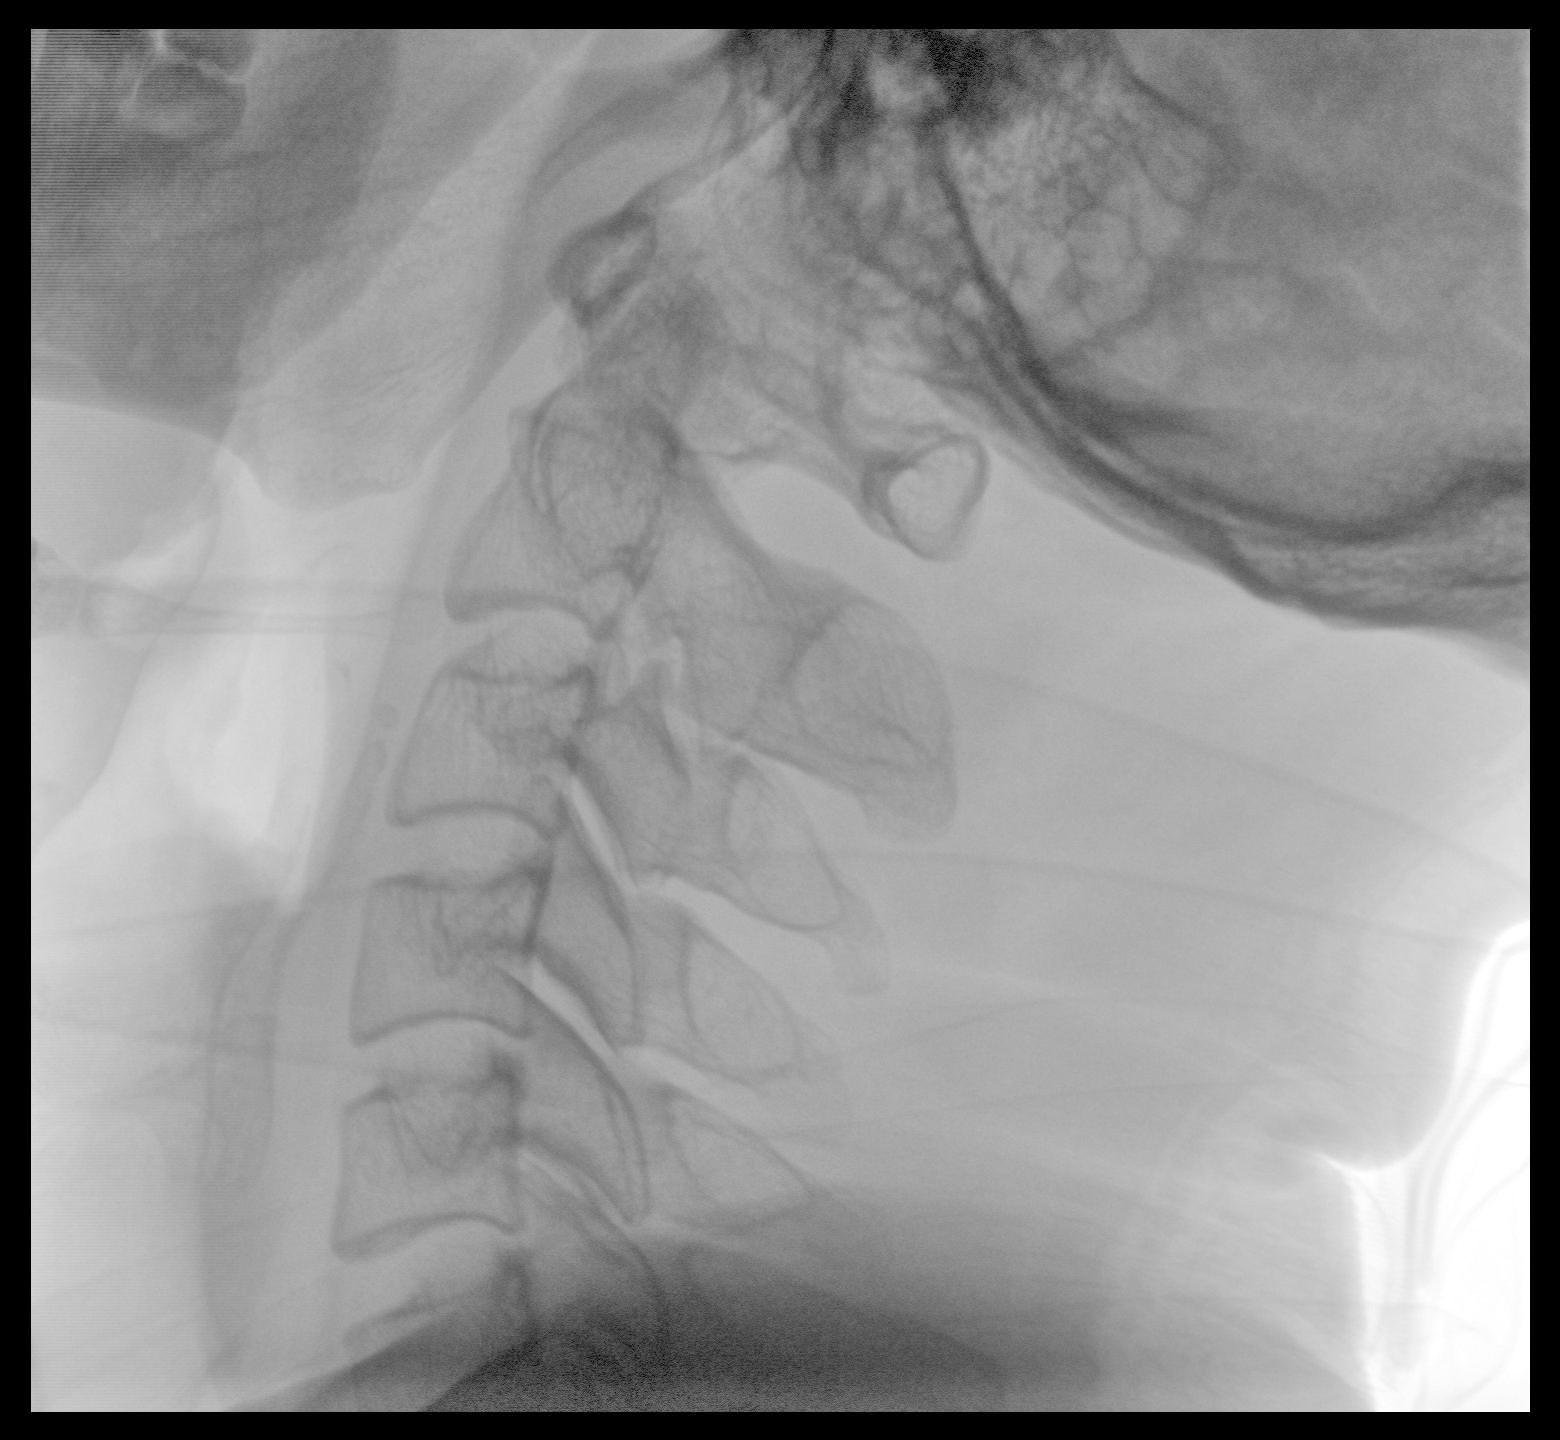

Clinical picture

臨床圖片

配備了兩種平板尺寸,大尺寸動態(tài)平板探測器成像面積較傳統(tǒng)平板探測器提升了25%以上,在視野需求大的手術(shù)中,便于醫(yī)生更好定位病灶點(diǎn),規(guī)劃手術(shù)方案,減少因視野范圍不足而多次透視、點(diǎn)片造成的不便。